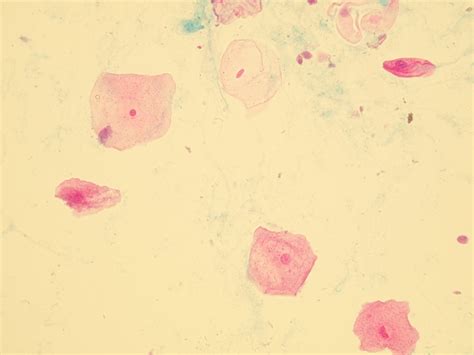

Squamous Epithelial Cells 610 are a specific subtype of squamous epithelial cells that exhibit unique characteristics. These cells are typically found in the stratified squamous epithelium, which is composed of multiple layers of cells. The number “610” in their designation refers to their specific morphological and functional properties, which distinguish them from other types of squamous epithelial cells.

• Flat and Scale-Like Shape: These cells have a flat, scale-like appearance, which allows them to form a tight, protective barrier.

• Diagnostic Markers: The presence and characteristics of Squamous Epithelial Cells 610 can serve as diagnostic markers for various diseases, including squamous cell carcinoma and other epithelial disorders.

• Squamous Cell Carcinoma: This is a type of cancer that arises from squamous epithelial cells. Squamous Cell Carcinoma can occur in various parts of the body, including the skin, respiratory tract, and digestive system. The malignant transformation of Squamous Epithelial Cells 610 is a critical step in the development of this cancer.

• Epithelial Dysplasia: This condition involves abnormal changes in the squamous epithelium, which can progress to cancer if left untreated. Squamous Epithelial Cells 610 play a role in the development and progression of epithelial dysplasia.